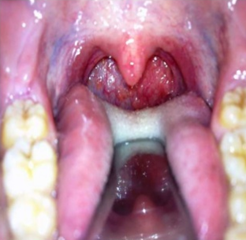

1) Absceso retrofaríngeo: Este diagnóstico, de no ser diagnosticado y tratado oportunamente, puede ser mortal debido a sus potenciales complicaciones: obstrucción de vía aérea, mediastinitis, neumonía aspirativa, absceso epidural, trombosis venosa yugular, erosión hacia la carótida y sepsis. Por lo tanto, hay que pensarlo como una posibilidad diagnóstica al enfrentar a un paciente que consulta por dolor de garganta en el Servicio de Emergencia. Se forma en el espacio entre la pared posterior de la orofaringe y la fascia prevertebral, y es mucho (MUCHO) más frecuente en la población infantil, pero también puede presentarse en adultos. Así como el absceso periamigdalino, también pueden presentar (además de odinofagia) voz engolada y trismus. Al examen físico podemos encontrarnos con aumento de volumen de la pared posterior de la faringe (figura 1), lo que no es fácil de ver, por lo que debemos tener un alto índice de sospecha. El examen de elección es el TAC de cuello con contraste. El manejo consiste en antibióticos EV (penicilina en dosis altas + metronidazol, ampicilina sulbactam, clindamicina, etc) y evaluación por otorrinolaringología para valorar eventual drenaje.